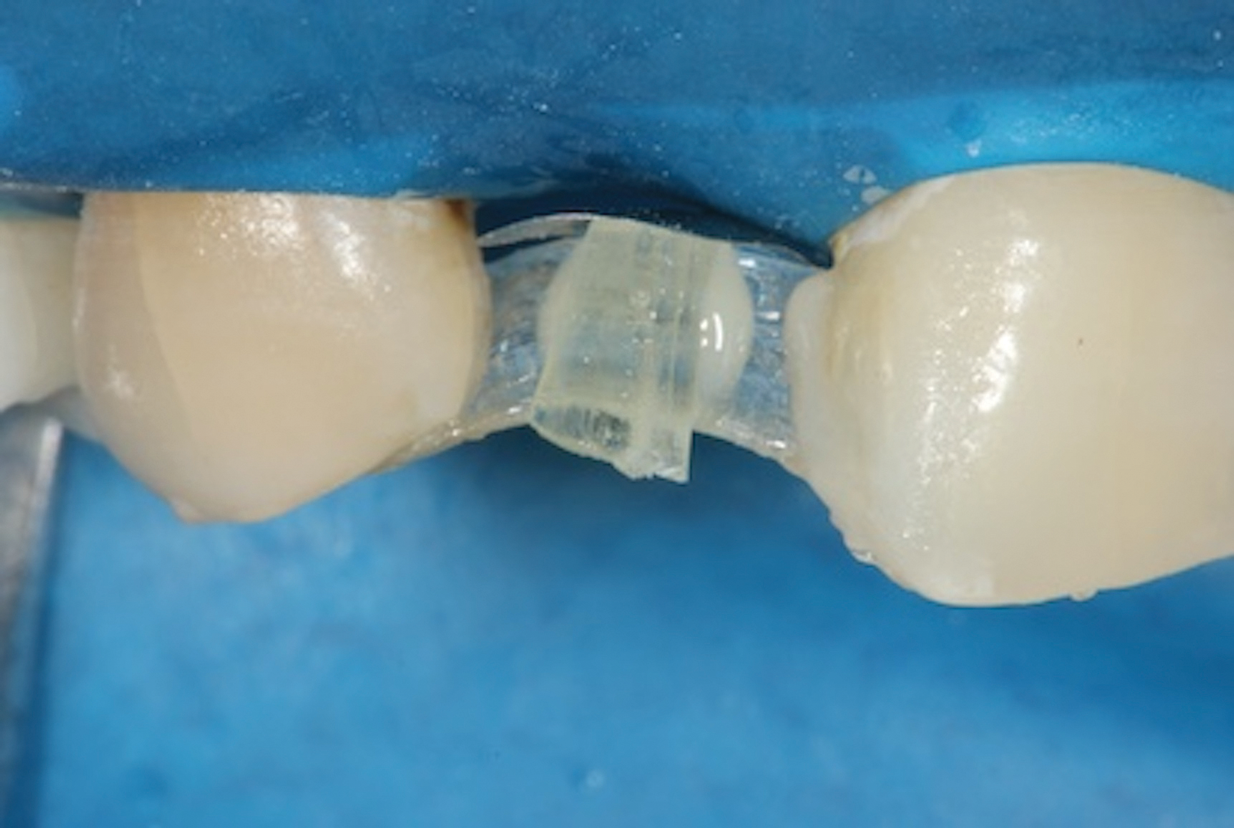

(9.) A sectional matrix band is positioned under the vertical fiber reinforcement such that its convex surface is touching the rubber dam in order to shape and position the tissue surface of the pontic as it is developed.

Figure 9

6. Begin Developing the Pontic

The most important part of the pontic regarding position, shape, and polish is the surface that will be in contact with the gingiva. An effective way of developing this contour is to employ a sectional matrix band. First, position the matrix band under the vertical fiber reinforcement such that its convex surface is touching the rubber dam (Figure 9). Next, cover the entire fiber assembly with an opaque shade of flowable composite. Direct the composite to flow under the fiber and along the matrix band to develop the desired emergence profile of the pontic. The contact with the band will create a smooth surface that will protect the soft tissue at the site without requiring any further handling (Figure 10 and Figure 11).